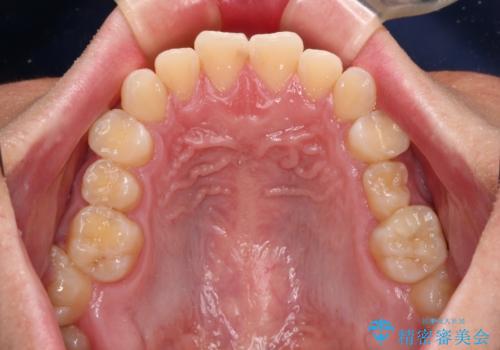

▼ 診断

・上顎左右の第二大臼歯が頬側へ転移し、シザーズバイト(scissors bite)の状態

・上顎左側第二小臼歯が90度捻転しており、噛み合わせに影響

**前歯のデコボコ(叢生)**が整い、歯列全体が美しく改善